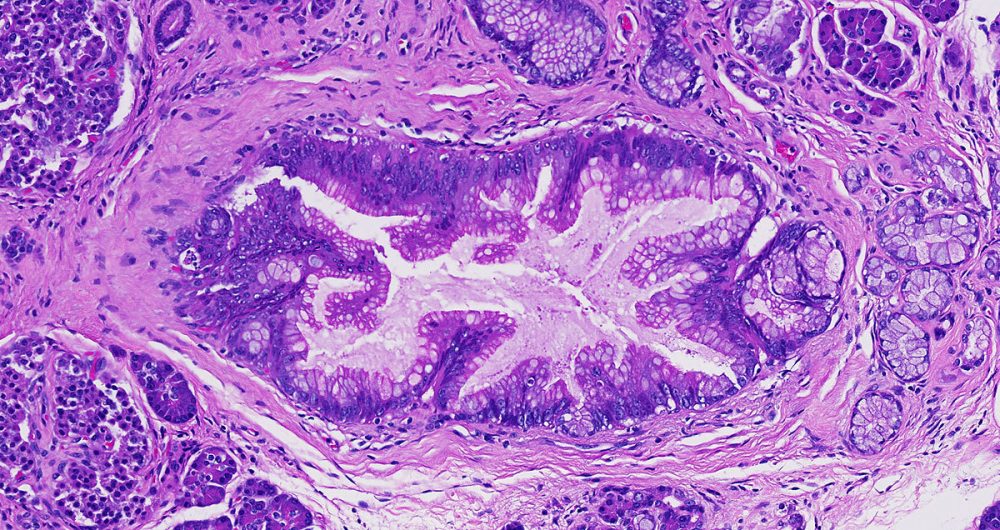

High-grade pancreatic intraepithelial neoplasia replaces the older term- PanIN-3.

A term used to describe certain tumors which grow in finger-like projections. Pathologists use this term to describe some precancerous lesions in the pancreas (intraductal papillary mucinous neoplasm).